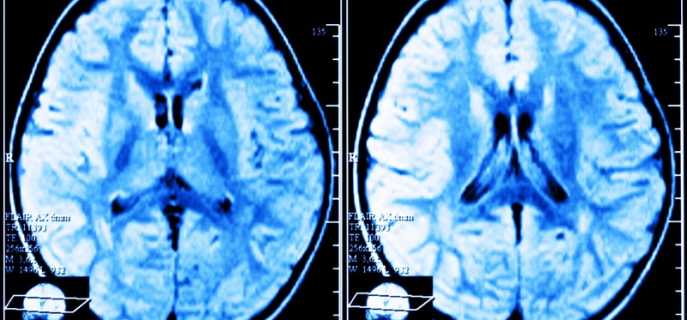

- проведение томографии полушарий головного мозга;

- магнитно-резонансная томография (дает возможность дифференцировать дисцикуляторный тип энцефалопатии);

Проведение МРТ позволяет выявить различные очаги недуга в белом веществе. Таким образом, болезнь можно выявить на ранней стадии, тем самым не упустив драгоценное время. Коварство заболевания заключается в том, что человек может жить и не знать о его наличии, поскольку симптомы могут возникать и исчезать на время, поэтому крайне важно проводить своевременную диагностику.